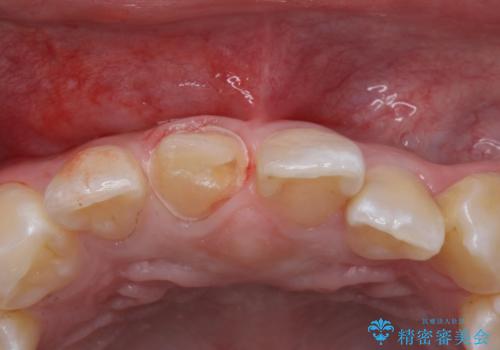

- 前歯のかぶせ物の色が気になるとのことで来院された患者様です。

セラミッククラウンで作り変えていきます。